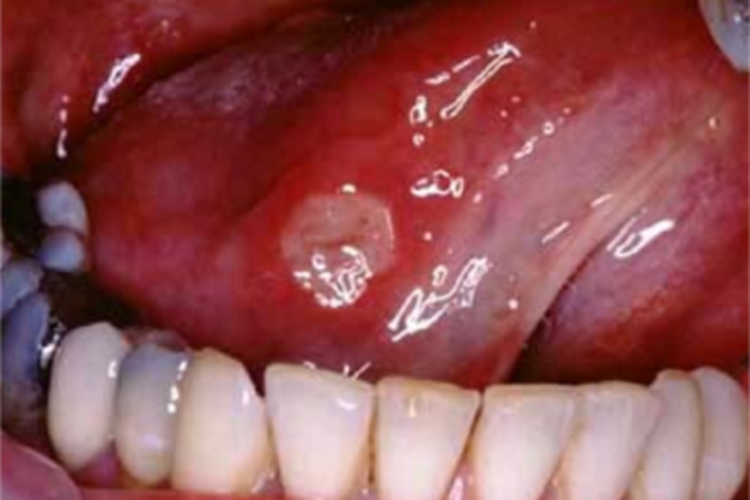

白塞病可发生在部分患者舌侧,表现为单个溃疡,表面附有黄白色的假膜,形状不规则,但是边界清楚,患者自觉疼痛。溃疡可能会影响进食,有自愈倾向,但会反复发作。